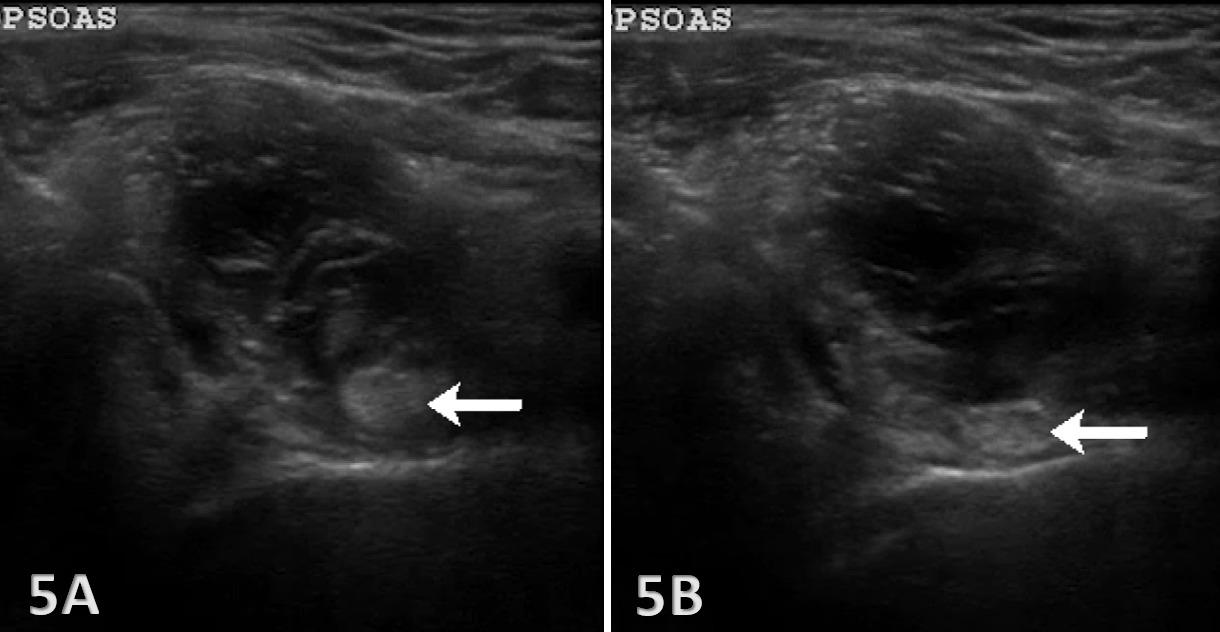

26. Ekstrand J, Lundqvist D, Davison M, D’Hooghe M, Pensgaard AM. Communication quality between the medical team and the head coach/manager is associated with injury burden and player availability in elite football clubs. Br J Sports Med 2019;53(5):304-308. doi:10.1136/ bjsports-2018-099411

27. Little C, Lavender AP, Starcevich C, et al. Understanding fear after an anterior cruciate ligament injury: a qualitative thematic analysis using the common-sense model. Int J Environ Res Public Health 2023;20(4). doi:10.3390/ijerph20042920

Solie B, Carlson M,

C,

Oh, My Quad: A Clinical Commentary And Evidence-Based Framework for the Rehabilitation of Quadriceps Size and Strength after Anterior Cruciate Ligament Reconstruction. IJSPT. 2024;19(12):1600-1628. doi:10.26603/001c.126191

Braidy

Solie1 a , Mitchell Carlson2 , Christopher Doney1 , Michael

Kiely

3 , Robert LaPrade4

1 Physical Therapy, Twin Cities Orthopedics, 2 Bioengineering Lab, Twin Cities Orthopedics , 3 Sports Science, Twin Cities Orthopedics, 4 Orthopedic Surgery, Twin Cities Orthopedics